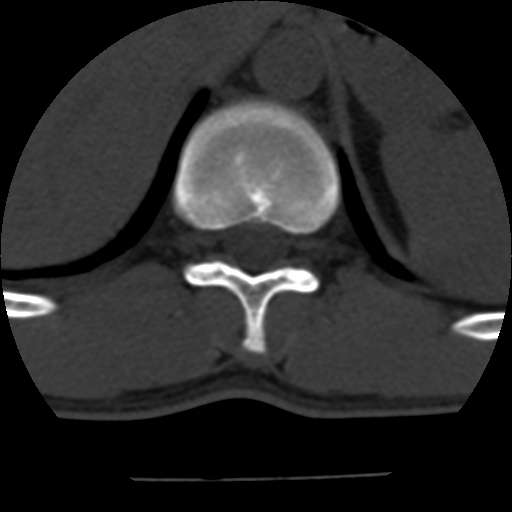

男,31岁,从6米高处坠落伤两天,腰背部疼痛,临床要求ct扫描胸10-腰1。请大家帮忙看看骨质有问题吗?

t12、l1锥体前缘轻度楔形变,平扫示椎体前缘骨小梁欠规整,第9幅图示椎体前缘骨质不连续,结合外伤史考虑椎体轻度压缩骨折。

从上查骨窗第九片椎体前缘皮质显示断裂.压缩骨折?